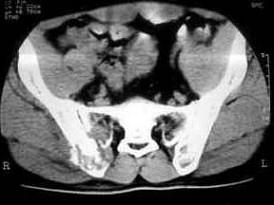

问题 患者 女,53岁,1个月前无明显诱因右髂部疼痛,为持续性隐痛,进行性加重,右下肢活动受限两周,体检右髂前上棘内侧可触及一3.0cm×2.0cm大小肿物,质韧,无活动,实验室检查无特殊,请结合所提供的图像,选择最佳选项 ( )

选项 A、髂骨纤维组织细胞瘤 B、骨母细胞瘤 C、骨髓炎 D、内生软骨瘤 E、骨结核

答案 A